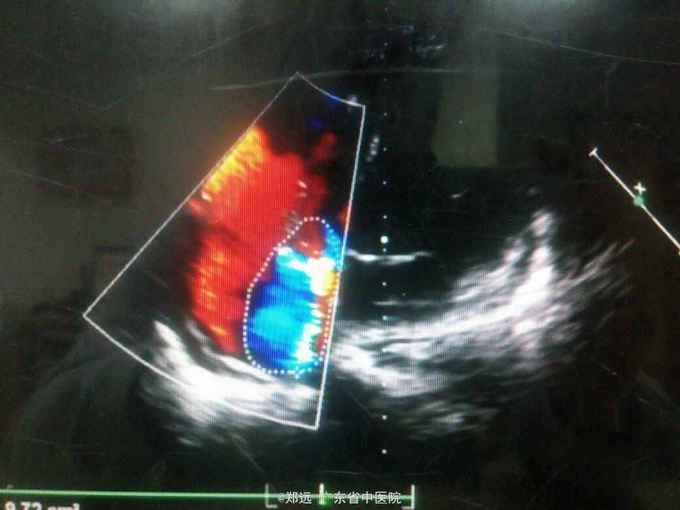

体查:双下肺湿啰音。三尖瓣区3/6级收缩期杂音。 胸部ct:双肺斑片结节影并空洞形成,左胸少量积液。血色素88克/升,白细胞11.48,中性粒81.3%,降钙素原14.84,ALT 121,AST 134.超声提示三尖瓣赘生物,三尖瓣大量返流。血培养金葡菌。

诊断:急性感染性心内膜炎,脓毒症,肺脓肿,丙型肝炎。 治疗:入院予万古霉素0.5克q6h,经治疗五日血象正常,降钙素原1.54,但仍反复高热,考虑肺脓肿合并阴性菌感染,加用头孢哌酮舒巴坦3克q12h,治疗五日仍有发热,血培养阴性,白细胞正常,降钙素原0.15,头孢哌酮舒巴坦改为美罗培南0.5克q8h,两日后无再发热,维持该方案至治疗四周后改予万古霉素0.5克q8h加美罗培南0.5克q12h继续治疗两周,复查超声提示三尖瓣熬生物较入院时缩小约三分之一,多次血培养阴性,胸部ct提示肺部炎症明显吸收予出院。出院后患者仍间发热,出院后约七周再次返院,查白细胞13.88,中性粒65.9%,血色素正常,降钙素原0.55,血培养提示溶血葡萄球菌,胸部ct示双肺多发感染灶,较前吸收,胸腔积液已吸收。予原万古霉素加美罗培南方案治疗,两日后无发热,治疗三周后多次血培养阴性,胸部ct提示肺部感染基本吸收,行三尖瓣赘生物切除并三尖瓣修补术,术中见三尖瓣后瓣瓣叶破坏严重,赘生物大小约2*1厘米。术后恢复良好,维持万古霉素加美罗培南治疗一周后改予万古霉素0.5克q8h加阿米卡星0.4克q12h治疗两周,赘生物及多次血培养阴性予出院。